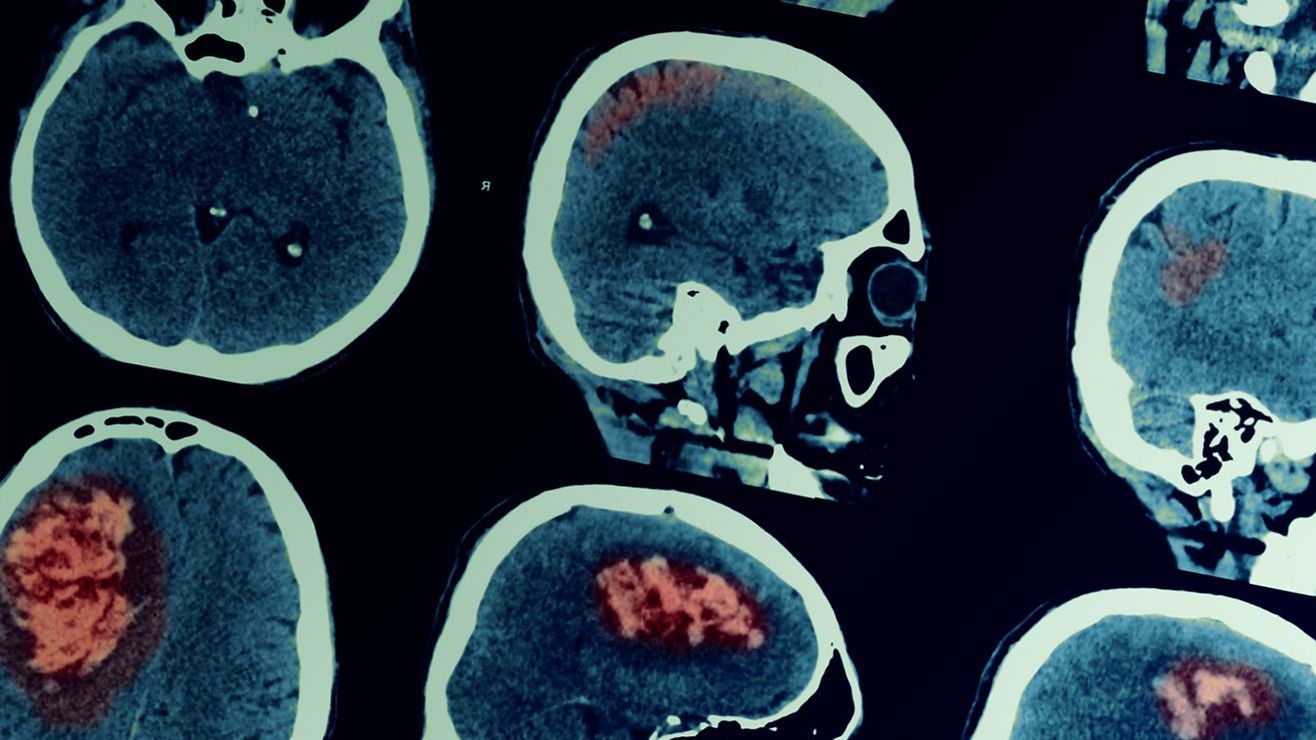

Descubre los síntomas y factores de riesgo de la hidrocefalia

Los signos de la hidrocefalia varían según el grupo etario de la persona

La hidrocefalia es un problema de salud muy grave y que tiene una incidencia muy notoria en el desarrollo del niño a lo largo de su vida. Si quieres conocer más sobre esta enfermedad, a continuación hablaremos sobre sus síntomas y factores de riesgo.